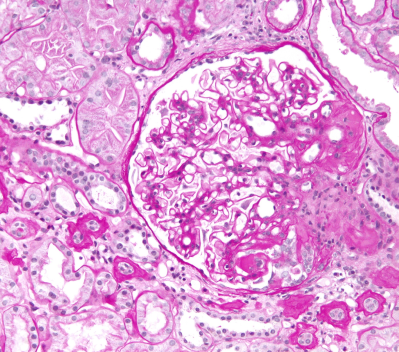

Световая микроскопия на современном этапе предполагает исследование почечной ткани после окрашивания различными методиками:

• окраска гематоксилином-эозином (для общего анализа структур);

• окраска по Массону (визуализация соединительной ткани);

• трихромальная окраска (для выявления фуксинофильных отложений);

• РАS-ШИК (для анализа мембран и дистрофии эпителиальных клеток);

• серебрение по Джонсу (исследование мембран);

• окраска по Вейгерту (исследование состояния сосудов);

• окраска конго-рот (идентификация амилоидных масс).

Отсутствие тех или иных методик окрашивания при выполнении световой микроскопии затрудняет постановку точного морфологического диагноза. Например, без выполнения серебрения по Джонсу нельзя сделать вывод о состоянии базальных мембран, что является важным компонентом верификации диагноза8.

Состояния, которые можно определить при помощи световой микроскопии:

• норма;

• сегментарный склероз/некроз;

• утолщение/нарушение структуры ГБМ;

• расширение мезангия/мезангиальная пролиферация;

• эндокапиллярная пролиферация;

• экстракапиллярная пролиферация.

Обзорное исследование биоптата включает оценку распространения и тяжести повреждений. Повреждение считается сегментарным для одного клубочка, если оно занимает менее 50% площади сосудистого клубочка, и глобальным, если занимает от 50 до 100% площади клубочка.

Тяжесть повреждения оценивается полуколичественно по балльной системе. Оценка варьируется от 0 до 3 или от 0 до 4 баллов, где 0 баллов означает отсутствие изменений, а 3 или 4 балла — выраженные изменения.

Основные гломерулярные повреждения, выявляемые при помощи световой микроскопии, включают увеличение или уменьшение размеров клубочка, изменения в количестве клеток клубочка, лобулярность (дольчатость), наличие некрозов, склероз, изменения клеток и базальной мембраны, изменение состояния просветов капилляров и Боуменовой капсулы, канальцев и интерстиция, а также сосудов.